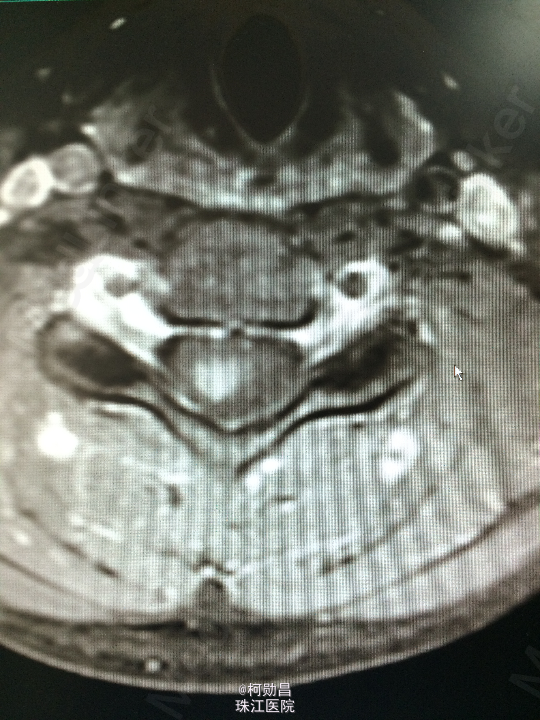

主诉:颈部疼痛伴右手麻木疼痛2月余 病史:患者缘于去年11月份无明显诱因出现右侧上肢乏力,右手小指及无名指疼痛麻木感,无头痛头晕,无间歇性跛行等,在当地医院行MR提示:颈椎椎管内占位性病变,予对症治疗后效果不佳。期间上述症状加重,遂至我院进一步诊治。

查体:颈椎下端棘突间轻压痛,颈椎活动受限,双臂丛牵拉试验阳性,压头试验阳性。四肢肌力5级,感觉:右侧前臂尺侧小指及无名指痛、触觉稍减退,余肢体及鞍区疼痛觉正常。反射:右侧肱二头肌腱反射亢进,左侧肱二头肌腱反射稍亢进,左侧肱三头肌腱反射活跃,双侧挠骨膜腱反射康静,双侧膝腱反射正常。余反射正常。病理征:右侧Hoffman征弱阳性,左侧Hoffman征正常,余征均正常。 辅助检查:颈4-6椎体水平髓内出血信号,海绵状血管瘤伴出血?

诊断:C5/6脊髓内海绵状血管瘤并出血。 处理:予手术切除治疗